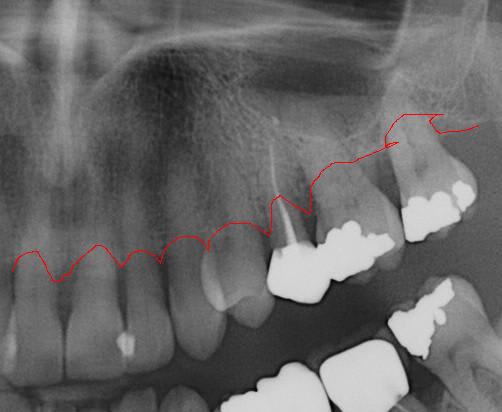

Les panos sont du départ, les photos sont après un nettoyage ...profond et soins.

Tout à fait d'accord avec le manque de calage par effondrement des spee. Il y a par contre égression du bloc incisif supérieur, d'où surcharge occlusal ne favorisant pas la paro, si on attend trop tout s'écroule. Une réingresser par de l'ortho sur un terrain paro fragile est super long, voir dangereux (aggravation de la paro), le choix de se passer d'ortho ici semble plutôt logique, il est urgent de régler l'occlusion et d’alléger le sur-guidage incisif (le rôle des provisoires molaire mandibulaire).

à l'examen des coupes pano, franchement je ne crois pas que ce soit le bon choix.